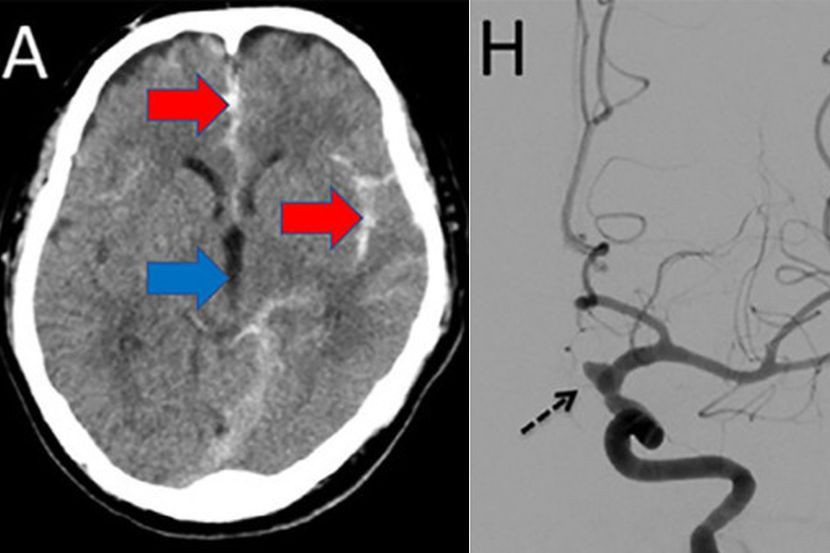

Pakar perubatan menjalankan imbasan tomografi berkomputer (CT scan) terhadap otaknya bagi mengetahui punca simptom yang dialaminya.

Keputusan mendapati dia mengalami pendarahan subarachnoid - sejenis strok yang mengancam nyawa yang disebabkan oleh pembuluh darah pecah dalam otaknya.